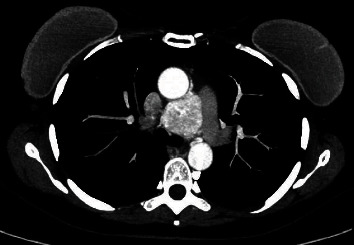

Paraganglioma of the middle mediastinum has a prevalence of 1%-2% of paragangliomas and less than 1% of mediastinal masses. It is generally asymptomatic and can easily be confused with other pathologies. The following is the case of a 50-year-old patient who, as an incidental finding, documented an injury between the aorta and the pulmonary artery, hypervascularized, which was embolized prior to surgery, which facilitated the complete resection of the lesion by sternotomy. With favorable evolution of the patient and discharge on the fourth postoperative day. A thorough review of the literature on the diagnostic and treatment approach to this pathology has been also carried out.

中纵隔副神经节瘤的发病率为副神经节瘤的 1%-2%,不到纵隔肿块的 1%。它一般没有症状,很容易与其他病变混淆。以下是一名 50 岁患者的病例,他偶然发现主动脉和肺动脉之间有损伤,血管扩张,手术前对其进行了栓塞,这有助于通过胸骨切开术完全切除病灶。术后第四天,患者康复出院。此外,还对该病症的诊断和治疗方法进行了全面的文献综述。